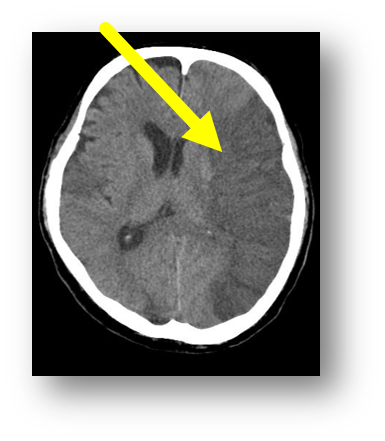

Q

hemorrhagic stroke